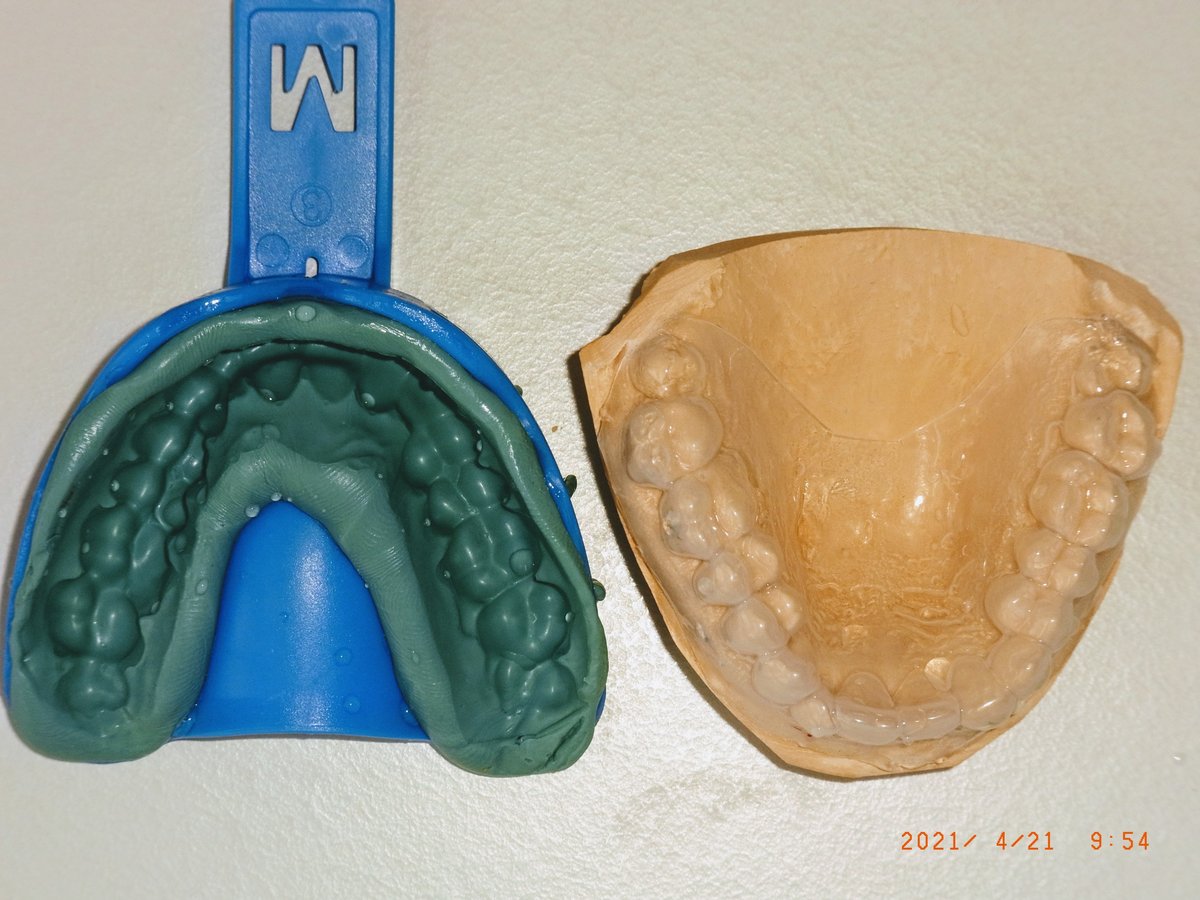

Vorabformung mit knetbarem Silikon im Rim-Lock-Einmalplastiklöffel (Fa. Dental Contact) auf dem Gipsmodell. Das knetbare Material füllt den Löffel über die Tiefziehfolie blasenfrei aus.

Fertiger KIL (links) neben dem Gipsmodell mit aufgezogener Tiefziehfolie (rechts). Der Löffel wird bis zu einige Tage vor der Verwendung im Eigenlabor gefertigt. Beschnitten wird der KIL im späteren Stumpfbereich gar nicht; in den übrigen Bereichen oral und lingual mit einem scharfen Küchenmesser bis ins gingivale Drittel der Zähne.